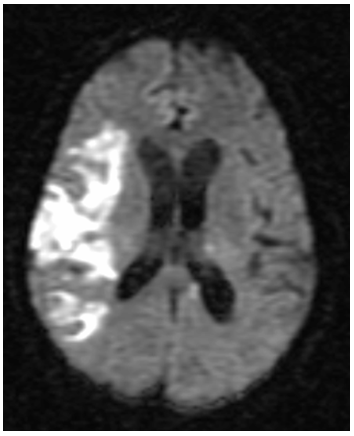

In the next hours, patient got progressively better so he only presented mild left hemiparesis and mild dysarthria. After 48hours, he presented again loss of consciousness followed by worsened dysarthria and nausea. Another CT scan was done, with a new hypodense lesion in left cerebellar hemisphere Figure 1. At that moment, neurological exam showed drowsiness, severe left hemiparesis, loss of sensitivity in left body, left Babinski sign, severe dysarthria and dysphagia.

Figure 1 Brain CT scan without contrast, showing right middle cerebral artery stroke and left cerebellar hypodense lesion.